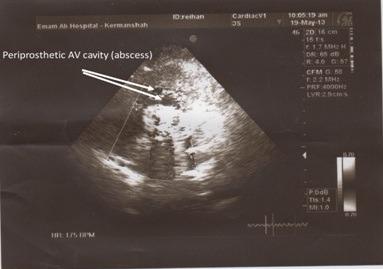

A rare case of prosthetic aortic valve endocarditis complicated with multiple fistula to peri aortic structure.

Multiple aorto-cardiac cavity communications is very rare but important complication of prosthetic aortic valve endocarditis. The case below illustrates multiple aorto-cardiac cavity fistula formation following prostethic aortic valve endocarditis presented with slowly progressive symptoms of heart failure. A brief review of surgical reconstruction and the existing literature are presented, including emphasis on pre and intra operative echocardiographic diagnosis and treatment.

多发性主动脉-心腔交通是人工主动脉瓣心内膜炎非常罕见但重要的并发症。以下病例说明了人工主动脉瓣心内膜炎后多发性主动脉-心腔瘘的形成,表现为心力衰竭的缓慢进展症状。本文简要回顾了手术重建及现有文献,重点强调术前和术中超声心动图诊断及治疗。